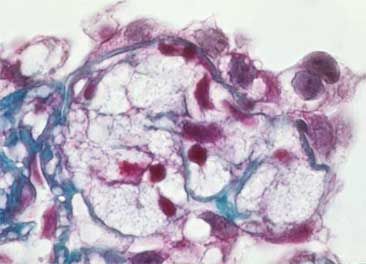

2. Aumento de la matriz con depositos de proteínas plasmáticas a lo largo de la pared capilar (hialinosis) que pueden ocluir las luces capilares

1. Imagen con tricrómico de Masson donde se observa hialinosis segmentaria con vacuolas lipídicas, observaadas en color rojizo. En las zonas adyacentes hay disminución o pérdida de las luces capilares.

2. Pueden existir gotas lipídicas y células espumosas

1. Imagen de un glomérulo teñido con tricromico de Masson donde se observan células espumosas, son células grandes con citoplasma claro vacuolado y pequeños núcleos.